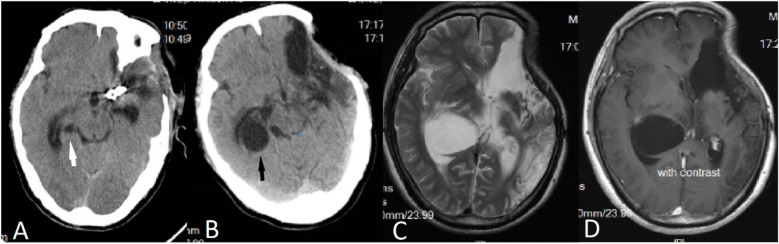

The simultaneous occurrence of intracranial aneurysms and intracranial arachnoid cysts is a rare clinical observation, with the majority of documented instances demonstrating ipsilateral presentation. In this report, we describe an atypical case involving the development of a secondary arachnoid cyst subsequent to the rupture of an intracranial aneurysm. Notably the cyst was situated contralaterally to the site of the aneurysm rupture and outside the surgical field. The patient's clinical history and imaging studies confirmedcorroborated the secondary nature of the cyst, which is postulated to have resulted from inflammatory responses triggered by a subarachnoid hemorrhage (SAH). The patient underwent neuroendoscopic partial resection of the cyst wall and lateral ventriculostomy, leading to a significant improvement in neurological dysfunction symptoms associated with the secondary arachnoid cyst. Follow-up cranial MRI demonstrated a substantial reduction in the cyst's volume, with no evidence of subsequent hydrocephalus or cyst enlargement. This case enhances the comprehension of the pathophysiological mechanisms underlying the formation of contralateral arachnoid cysts subsequent to aneurysm rupture and emphasizes the necessity of acknowledging arachnoid cysts as potential delayed complications associated with aneurysmal subarachnoid hemorrhage (aSAH).

颅内动脉瘤和颅内蛛网膜囊肿同时发生是一种罕见的临床观察,大多数记录的病例显示同侧表现。在这个报告中,我们描述了一个不典型的病例,涉及颅内动脉瘤破裂后继发性蛛网膜囊肿的发展。值得注意的是,囊肿位于动脉瘤破裂部位的对侧和手术野外。患者的临床病史和影像学检查证实了囊肿的继发性,推测是由蛛网膜下腔出血(SAH)引发的炎症反应引起的。患者接受了神经内窥镜部分切除囊肿壁和侧脑室造口术,继发性蛛网膜囊肿相关的神经功能障碍症状明显改善。后续颅脑MRI显示囊肿体积明显缩小,未见脑积水或囊肿增大。本病例加强了对动脉瘤破裂后对侧蛛网膜囊肿形成的病理生理机制的理解,并强调了将蛛网膜囊肿视为动脉瘤性蛛网膜下腔出血(aSAH)相关的潜在延迟并发症的必要性。